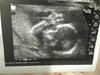

Ja już po połówkowym,obecnie 22+2 tc. Ja mam hashi,więc tsh szaleje. Własnie wróciłam od endo onkol. i okazało się,że mi się bardzo pogorszyły wyniki. Dostałam zwiększony letrox do 75.

Oprócz tego pytałam o szanse na kp. Niestety...tylko 20% szans z obecną prolaktyną :/